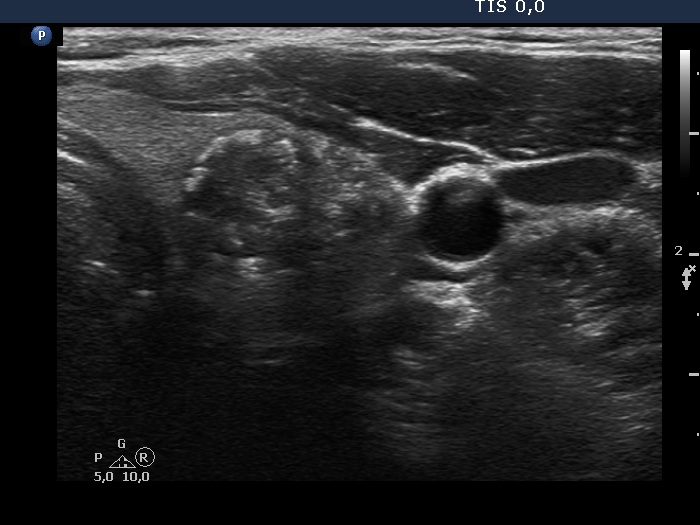

Right lobe, longitudinal scan

Left lobe, another transverse scan. Based on the acoustic shadow, the nodule must contain macrocalcification.